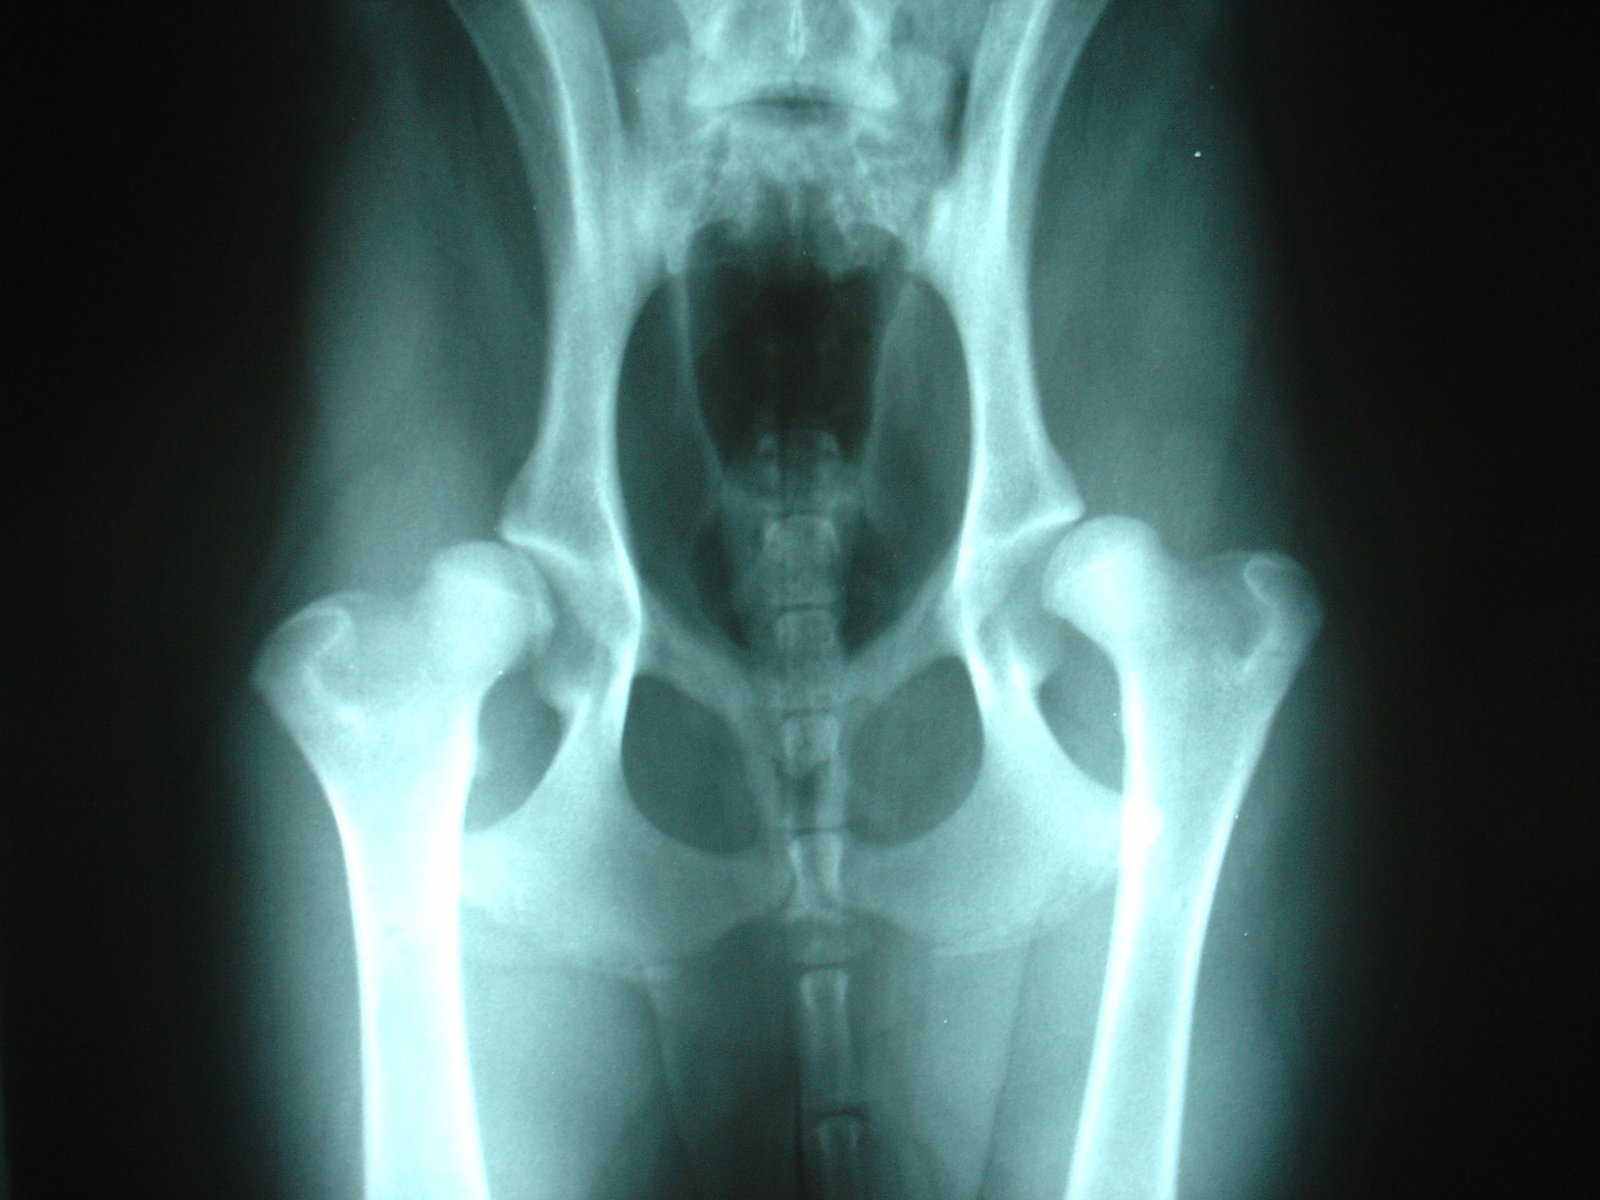

El ambiente competitivo de las exposiciones caninas fomenta un enfoque de cría que puede ser perjudicial. La diversidad genética se reduce a medida que los criadores seleccionan características específicas, lo que puede agravar problemas de salud hereditarios. Enfermedades como la displasia de cadera y otros trastornos genéticos están siendo más comunes entre los perros de exposición, incluido el Presa Canario.

Originalmente criado para el trabajo y la protección, la funcionalidad del Presa Canario está siendo opacada por su apariencia. Este cambio amenaza la supervivencia de los rasgos históricos de la raza, ya que los criadores de exposiciones a menudo pasan por alto los exámenes de salud vitales en favor de mejorar las características físicas que atraen a los jueces.

X-ray of a dog with hip dysplasia.